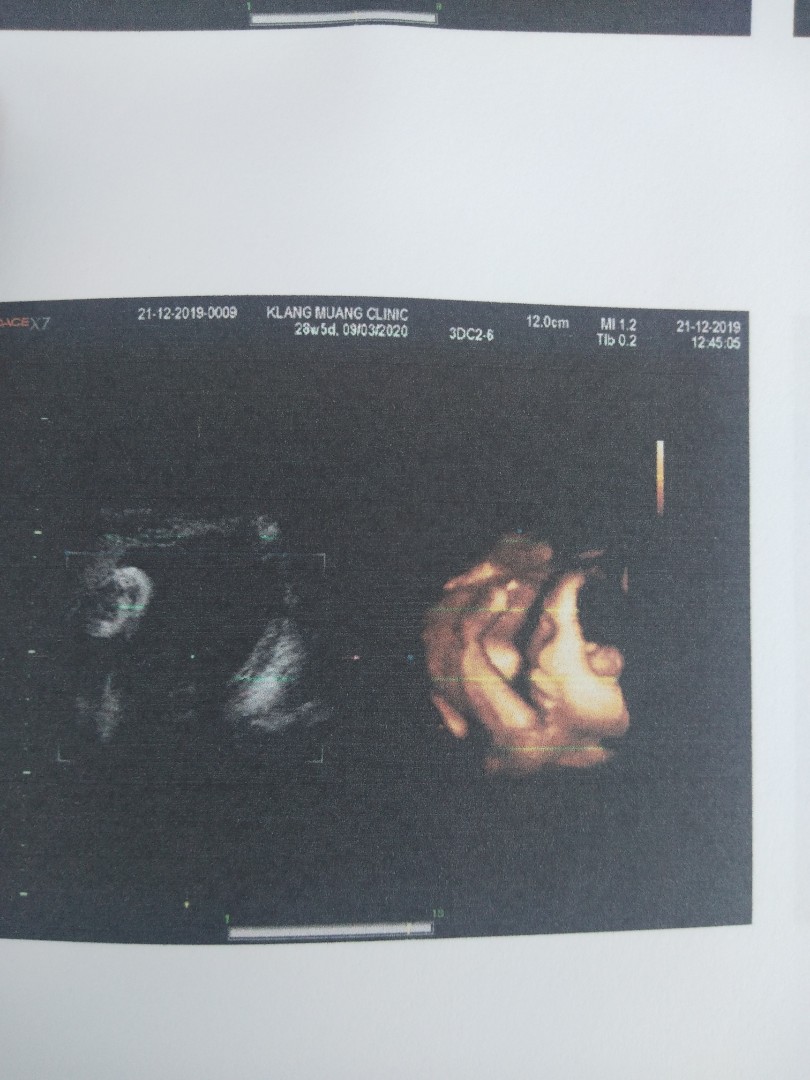

ซาวตอน 28 w คะ ส่วนตัวคิดว่า ค่อนข้างชัดนะคะ เห็นน้องยิ้ม ขยับเล็กน้อย ได้เช็คอวัยวะ บางส่วน และได้รูปภาพ น่ารักๆ เก็บไว้คะ ❤️

ของเราไปตอน30วีคค่าน้องกลับหัวอยู่ เห็นหน้าน้องครึ่งนึงค่ะรกบังหน้า หมอเลยให้มาดูแต่2มิติได้แบบนี้มา จะได้ไม่เสียเงินเพิ่ม

ซาวด์ตอนกลับหัวแล้วค่ะแม่ 32สัปดาห์ พอดีแม่เข้ากลางคืน กลางวันน้องหลับเลยได้ออกมาแบบนี้ค่ะ

ต้องแล้วแต่น้องค่ะว่าจะหันหน้าไปทางไหน 31 สัปดาห์ กลับหัวแล้ว